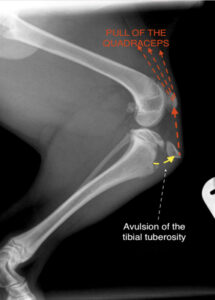

In October 2022, Ozzy sustained a tibial tuberosity avulsion fracture (TTAF), requiring surgery on both rear legs. In tibial tuberosity avulsion — seen in young canines — a small piece of bone known as the tibial tuberosity is displaced from the shinbone or tibia by the pull of the quadriceps muscle group. This type of injury is common in puppies, as they are in an active growth phase and their bones are not as strong as those of adult dogs. In most cases, orthopedic surgery is essential for tibial tuberosity avulsion recovery in dogs because the quadriceps muscles will continue to pull the bone from its place.